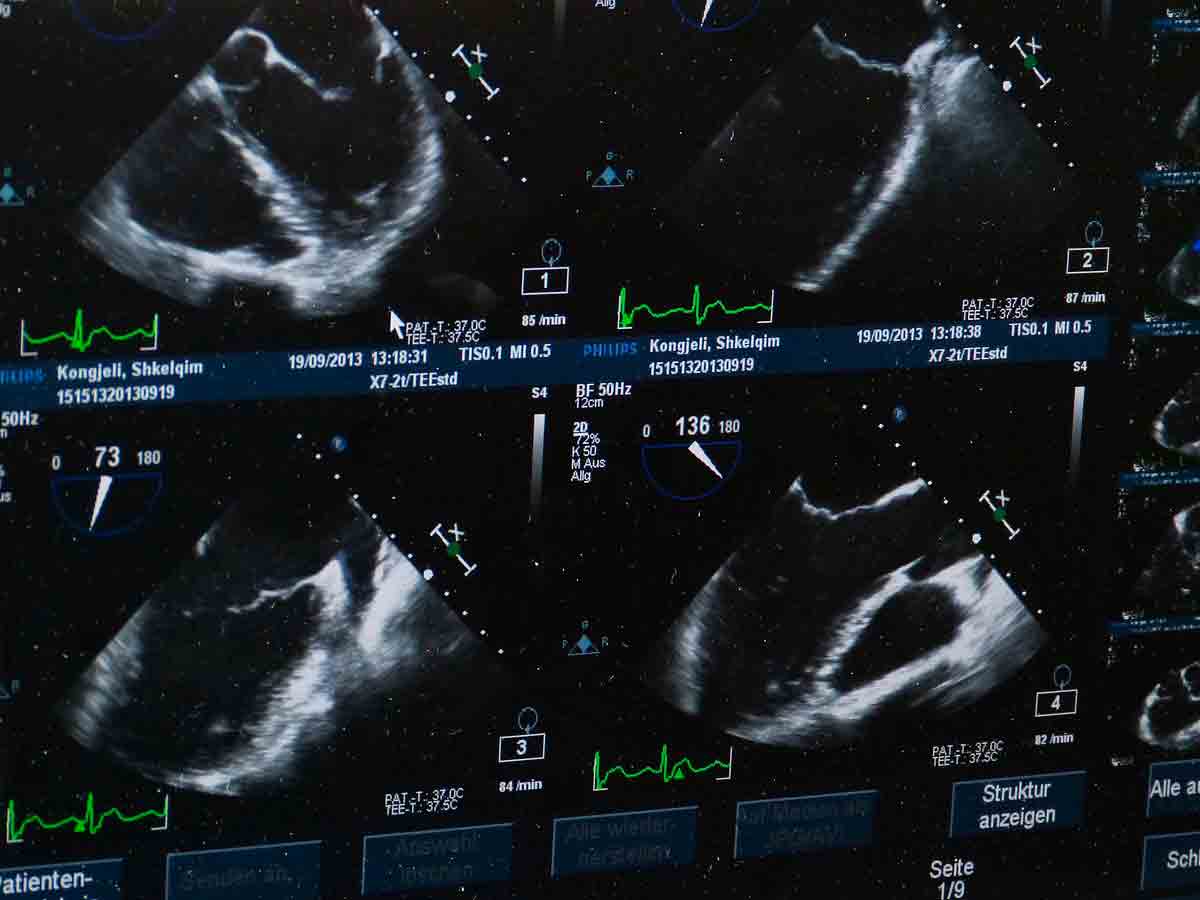

Una mujer egipcia ha recibido la noticia de que está embarazada de nueve bebés , un caso extremadamente raro según confirmaron especialistas tras un diagnóstico ecográfico reportado por la cadena Al Arabiya.

Los médicos señalan que esta gestación múltiple se habría originado a raíz del consumo de medicamentos para la infertilidad sin supervisión médica. Estos tratamientos estimulan los ovarios y pueden provocar la liberación y fecundación de múltiples óvulos a la vez.